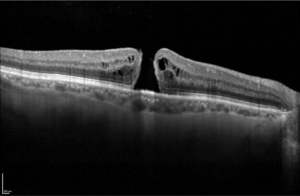

Coupe maculaire en OCT sans anomalie, avec une dépression centrale en entonnoir (flèche)

Coupe maculaire en OCT avec interruption de la rétine centrale, formant un trou (flèche)

Coupe maculaire en OCT avant opération du trou maculaire : interruption de la rétine (flèche)

Coupe maculaire en OCT après l’opération du trou maculaire : réapparition de l’entonnoir maculaire (flèche)